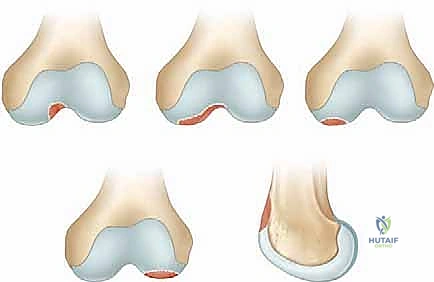

مراحل تطور OCD

يمر التهاب العظم والغضروف السالخ بأربع مراحل سريرية وإشعاعية:

* المرحلة 1: تليّن الغضروف المفصلي مع بقائه سليماً من الخارج، مع وجود وذمة (تورم) في العظم تحته.

* المرحلة 2: انفصال جزئي للقطعة العظمية الغضروفية، لكنها لا تزال ثابتة في مكانها.

* المرحلة 3: انفصال كامل للقطعة، لكنها لا تزال مستقرة داخل التجويف العظمي (السرير العظمي).

* المرحلة 4: خروج القطعة العظمية الغضروفية من مكانها لتسبح بحرية داخل المفصل (Loose Body)، مما يسبب تعليقاً ميكانيكياً (Locking) للركبة.